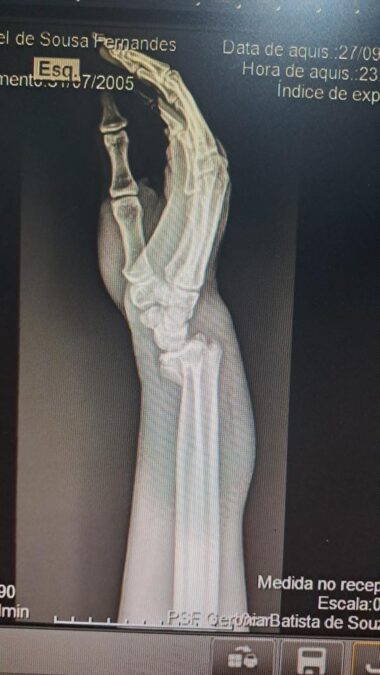

Segundo relato do jovem entregador, no último sábado, quando trabalhava fazendo entregas, ele passou próximo à antiga guarida, saída para Luziânia, quando cachorro grande entrou na frente de sua moto e o fez cair. Na queda, infelizmente, ele fraturou um dos pulsos.

Agora, o motociclista aguarda por uma cirurgia. Ele informou que além do cão em que ele colidiu, existiam outros quatro cães nas proximidades onde aconteceu o acidente.